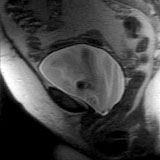

Sagittal T2-weighted image obtained during straining. Note descent of the bladder.

The patient was instructed to alternately strain and relax as a series of sub-second T1-weighted images were obtained, showing the dynamic motion of the pelvic structures with straining.